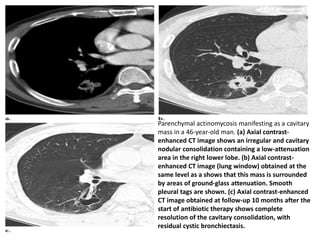

Parenchymal actinomycosis manifesting as a cavitary

mass in a 46-year-old man. (a) Axial contrast-

enhanced CT image shows an irregular and cavitary

nodular consolidation containing a low-attenuation

area in the right lower lobe. (b) Axial contrast-

enhanced CT image (lung window) obtained at the

same level as a shows that this mass is surrounded

by areas of ground-glass attenuation. Smooth

pleural tags are shown. (c) Axial contrast-enhanced

CT image obtained at follow-up 10 months after the

start of antibiotic therapy shows complete

resolution of the cavitary consolidation, with

residual cystic bronchiectasis.

Parenchymal actinomycosis manifestingas a cavitary mass in a 46-year-old man. (a) Axial contrast- enhanced CT image shows an irregular and cavitary nodular consolidation containing a low-attenuation area in the right lower lobe. (b) Axial contrast- enhanced CT image (lung window) obtained at the same level as a shows that this mass is surrounded by areas of ground-glass attenuation. Smooth pleural tags are shown. (c) Axial contrast-enhanced CT image obtained at follow-up 10 months after the start of antibiotic therapy shows complete resolution of the cavitary consolidation, with residual cystic bronchiectasis.